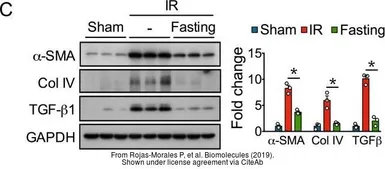

The data was published in the journal PLoS One in 2019. PMID: 30695033